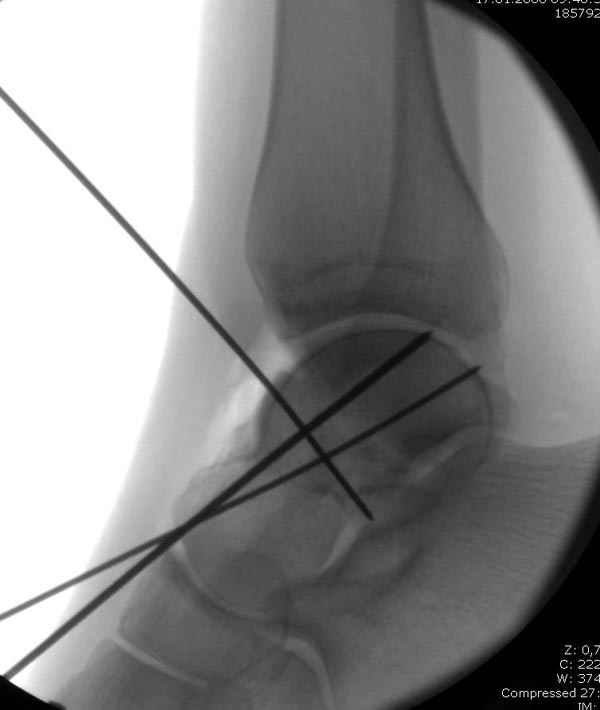

Вдогонку по поводу перелома таранной кости, больная 81, не страдает диабетом, перелом закрытый, в первый же день поступления ограничились временным наружным фиксатором (как на снимке).

Планировалась открытая фиксация после спадения отека, но больная пожелала лечиться по месту жительству в другом штате..

Из-за отека на стопе тактика лечения у всех была

одинаковая: временная наружная фиксация до спадения отека, при изолированных переломах они выписывались домой и через дней 7 госпитализировались на оперативное лечение.

Примеры на снимке...